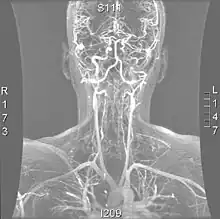

| Cerebral Angiogram obtained using an iodine based contrast medium | |

Cerebral atherosclerosis is a type of atherosclerosis where build-up of plaque in the blood vessels of the brain occurs. Some of the main components of the plaques are connective tissue, extracellular matrix, including collagen, proteoglycans, fibronectin, and elastic fibers; crystalline cholesterol, cholesteryl esters, and phospholipids; cells such as monocyte derived macrophages, T-lymphocytes, and smooth muscle cells.[1] The plaque that builds up can lead to further complications such as stroke, as the plaque disrupts blood flow within the intracranial arterioles. This causes the downstream sections of the brain that would normally be supplied by the blocked artery to suffer from ischemia.[2] Diagnosis of the disease is normally done through imaging technology such as angiograms or magnetic resonance imaging. The risk of cerebral atherosclerosis and its associated diseases appears to increase with increasing age;[3] however there are numerous factors that can be controlled in attempt to lessen risk.[4]

Due to positive remodeling the plaque build-up shown on angiogram may appear further downstream on the x-ray where the luminal diameter would look normal even though there is severe narrowing at the real site. Because angiograms require x-rays to be visualized the number of times an individual can have it done over a year is limited by the guidelines for the amount of radiation they can be exposed to in a one-year period.[2]

Magnetic resonance imaging has the ability to quantify the plaque anatomy and composition. This allows physicians to determine certain characteristics of the plaque such as how likely it is to break away from the wall and become an embolus. MRI does not use ionizing radiation, so the number of times that it is used on a single person is not a concern; however since it uses strong magnetic fields those who have metal implants cannot use this technique.[1][2]